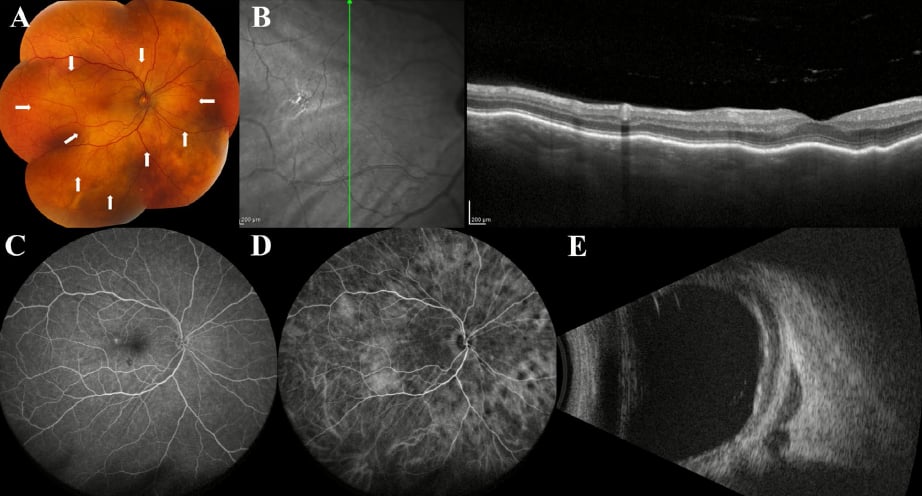

1. 眼底照相:寻找“极光”与“串珠”

在传统的眼底照相中,VRL 表现为玻璃体内的细胞浸润。其中,“极光模式”(Aurora Borealis pattern)对 VRL 具有极高的特异性。这种模式描述为大量的肿瘤细胞沿玻璃体纤维呈放射状排列,在光照下产生类似极光的外观。如果您或家人在检查报告中看到类似描述,应高度怀疑淋巴瘤而非普通的炎症。此外,“串珠”模式也是特征之一,表现为细纤维连接的物质簇,虽然也可见于结节病,但仍需警惕。

2. 光学相干断层扫描(OCT):微观下的“侦探”

OCT 是目前诊断 VRL 最不可或缺的工具。100% 的眼肿瘤专家认为 OCT 是识别 VRL 的必要程序。在 OCT 图像上,视网膜前沉积物(特异性达 92.5%)和视网膜内垂直高反射病变(VHRL)是诊断的“金标准”线索。这些病变代表了肿瘤细胞在视网膜层间的浸润。值得注意的是,虽然 VRL 会引起严重的玻璃体混浊,但患者的视力往往保持得出乎意料的好,这与葡萄膜炎常伴随的黄斑水肿形成了鲜明对比。

1. EDI-OCT 的深度探测

增强深度成像 OCT(EDI-OCT)可以穿透视网膜,观察脉络膜的厚度与形态。CL 在 OCT 上有一种非常形象的描述——“晕船样”模式(Sea-sick configuration)。这是由于脉络膜被肿瘤细胞弥漫性浸润,导致表面呈现出波浪状的起伏。这种地形图般的波动与肿瘤的厚度直接相关。

2. B 型超声:评估眼外扩展

超声检查在评估 CL 时具有不可替代的价值。它能清晰显示脉络膜的弥漫性、低回声增厚。更重要的是,超声可以检测到巩膜外延伸(ESE),即肿瘤是否已经穿透眼球壁向眼眶扩散。这对于制定手术或放疗方案至关重要。